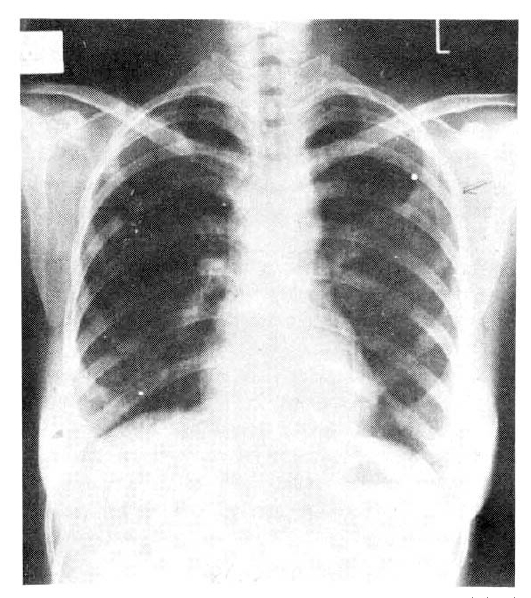

On admission, she was afebrile, and her respiratory rate was 34/min. On auscultation of the chest, there were inspiratory rales on all lung fields, but no wheezing or friction rub. The peripheral blood hemoglobin was 14.5gm/dl, hematocrit 44, WBC 14,800 (poly 74%, lymphocyte 14%, eosinophil 7%), and ESR was 43mm/hr. The chest x-ray showed bilateral patchy infiltrates (Fig. 1), No organisms were found on sputum smears and cultures. After treatment with erythromycin, she had a prompt recovery and was discharged. At the time of discharge, she was in an asymptomatic condition and had normal vital signs. The chest was clear on auscultation. The peripheral leukocyte count and ESR were normal.

Chest x-ray on admission: Bilateral patahy infiltrations are seen, more in Lt upper and Rt lower lung field.